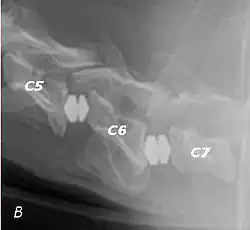

Wobbler disease is probably inherited in the Borzoi, Great Dane, Doberman, and Basset Hound.[2] Instability of the vertebrae of the neck (usually the caudal neck) causes spinal cord compression. In younger dogs such as Great Danes less than two years of age, wobbler disease is caused by stenosis (narrowing) of the vertebral canal[3] related to degeneration of the dorsal articular facets and subsequent thickening of the associated joint capsules and ligaments.[1] A high-protein diet may contribute to its development.[4] In middle-aged and older dogs such as Dobermans, intervertebral disc disease leads to bulging of the disc or herniation of the disc contents, and the spinal cord is compressed.[3] In Great Danes, the C4 to C6 vertebrae are most commonly affected; in Dobermans, the C5 to C7 vertebrae are affected.[5]

The disease tends to be gradually progressive. Symptoms such as weakness, ataxia, and dragging of the toes start in the rear legs. Dogs often have a crouching stance with a downward flexed neck. The disease progresses to the front legs, but the symptoms are less severe. Neck pain is sometimes seen. Symptoms are usually gradual in onset, but may progress rapidly following trauma.[6] X-rays may show misaligned vertebrae and narrow disk spaces, but it is not as effective as a myelogram, which reveals stenosis of the vertebral canal. Magnetic resonance imaging has been shown to be more effective at showing the location, nature, and severity of spinal cord compression than a myelogram.[7] Treatment is either medical to control the symptoms, usually with corticosteroids and cage rest, or surgical to correct the spinal cord compression. The prognosis is guarded in either case. Surgery may fully correct the problem, but it is technically difficult and relapses may occur. Types of surgery include ventral decompression of the spinal cord (ventral slot technique), dorsal decompression, and vertebral stabilization.[8] One study showed no significant advantage to any of the common spinal cord decompression procedures.[9] Another study showed that electroacupuncture may be a successful treatment for Wobbler disease.[10] A new surgical treatment using a proprietary medical device has been developed for dogs with disc-associated wobbler disease. It implants an artificial disc (cervical arthroplasty) in place of the affected disc space.[11]

Wobbler disease is definitively diagnosed by x-ray, nuclear scintigraphy or bone scan. X-rays will show channel widening or filling the easiest and are often most cost-effective to horse owners. X-rays will also show any structural anomaly, arthritis, facet remodeling, or bone spurs present. Preliminary diagnosis can be made by ultrasound but x-rays are needed to measure the true depth of facet involvement. For extent of damage to associated structures, veterinarians may opt to have the horse undergo a bone scan or nuclear scintigraphy.